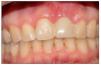

Figura 7. Paciente rehabilitado.

En todos los casos intervenidos mediante ROG en conjunto con injerto conectivo se logró una mejora y equiparación de los contornos periimplantarios con las piezas vecinas u homólogas, en relación con la posición del margen periimplantario y cénit.

Figura 14.Paciente rehabilitado.

Una vez rehabilitados los implantes, se equiparó la posición del margen gingival, cénit y la relación coronaria con respecto a la pieza vecina u homologa en todos los casos intervenidos.

Al evaluar el grado de satisfacción de los pacientes con respecto a la restauración final, la totalidad de los pacientes indicaron estar altamente satisfechos con su estética y con la integración de la restauración con respecto al resto de las piezas dentarias.